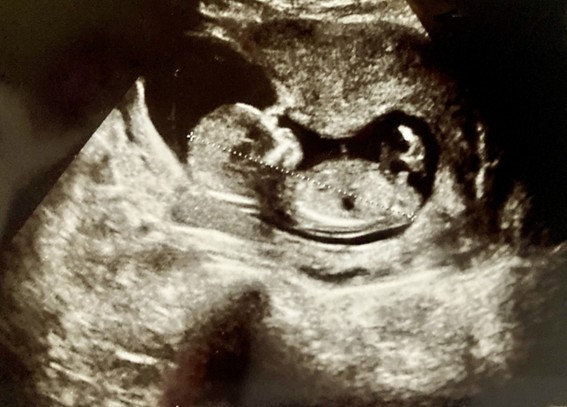

経腹エコーとはお腹に超音波を当てて、内部の様子を画像化する検査です。妊婦健診でも行われる検査で、赤ちゃんの成長や発達の様子を確認したり、異常の発見をしたりするのに役立ちます。

エコー(超音波)検査で写っているのは赤ちゃんの断面図です。位置や角度など超音波の当て方、赤ちゃんの姿勢によっても写り方が変化します。

画像はモノクロで、白・グレー・黒の3色からなります。組織によっても超音波の跳ね返しが異なるため、反射が強い固い組織は白、そうでない組織は黒っぽく写ります。